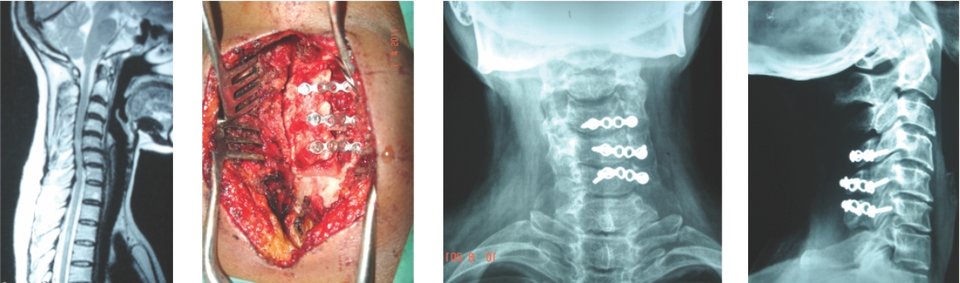

A very young pt of 25 years old, belonging to very good family, an engineer, had

tuberculosis of cervical

spine with destruction of C7 vertebra

if he would not get urgent attention and surgery, he could have landed up in developing

paraplegia

he was operated from front of the neck, a new vertebra(tricortical bone graft) was

put and fixed with plate

now he is doing very well in his life

Paeditric Koch’s - Spine